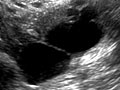

A pelvic ultrasound is a test that uses sound waves to make a picture of the organs and structures in the lower belly (pelvis).

Organs and structures that are solid and uniform (such as the uterus, ovaries, or prostate gland) or that are fluid-filled (such as the bladder) show up clearly on a pelvic ultrasound. Bones may block other organs from being seen. Air-filled organs, such as the intestines, can make the image less clear.

In all of these ultrasounds, the transducer sends the reflected sound waves to a computer, which makes them into a picture that is shown on a video screen. Ultrasound pictures or videos may be saved as a permanent record.

- Confirm a pregnancy and see if it is in the uterus. Pelvic ultrasound may be used early in pregnancy to check the age of the pregnancy or to find a tubal pregnancy (ectopic pregnancy) or multiple pregnancy.